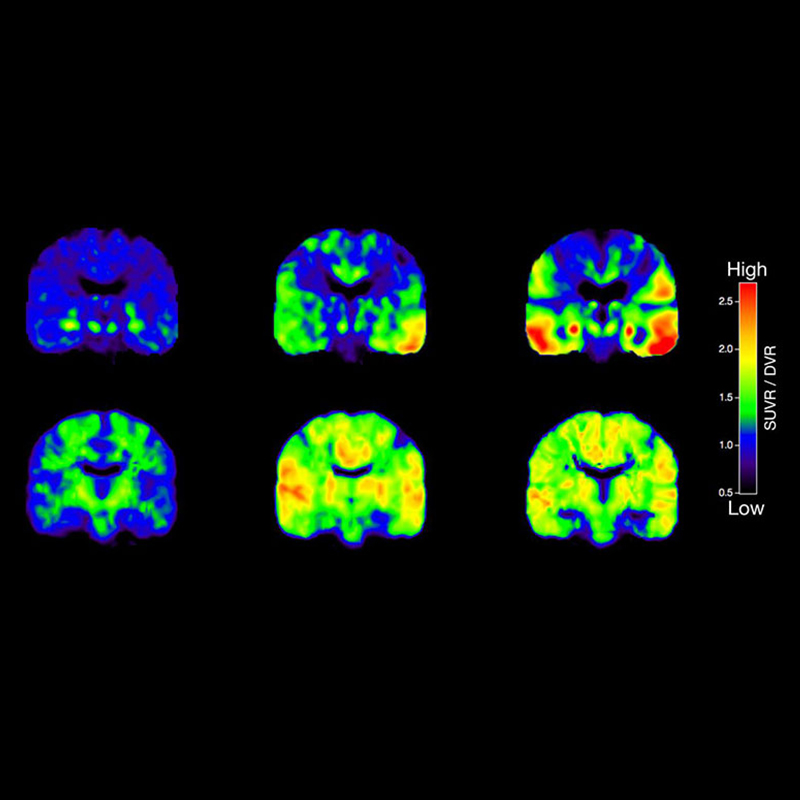

Beyin fonksiyonlarını (fMRI), doku metabolizmasını (MR spektroskopi) ve kan akışını değerlendirmek için uygundur.

İnme, tümörler, epilepsi, Alzheimer gibi nörolojik hastalıkların teşhis ve takibinde çok etkilidir.

o Beyin fonksiyonlarını (fMRI), doku metabolizmasını (MR spektroskopi) ve kan akışını değerlendirmek için uygundur.

o İnme, tümörler, epilepsi, Alzheimer gibi nörolojik hastalıkların teşhis ve takibinde çok etkilidir.